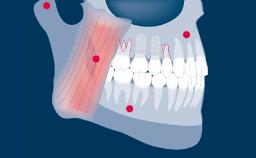

Implant impressions are important for the fabrication of dental prostheses. The aim of implant impressions is accurate transfer of the intra-oral implant situation to the dental laboratory. It is possible to record the implant situation with conventional analog impression techniques, or using digital technologies.

All implant impression techniques employ a variation of the pick-up or transfer impression technique sometimes used in conventional, tooth-borne prosthodontics.

The impression, whether it follows a conventional (that is, analog) or digital workflow, then records this information in relation to the surrounding hard and soft tissues. This module will deal with conventional impression techniques and all of the parameters involved.